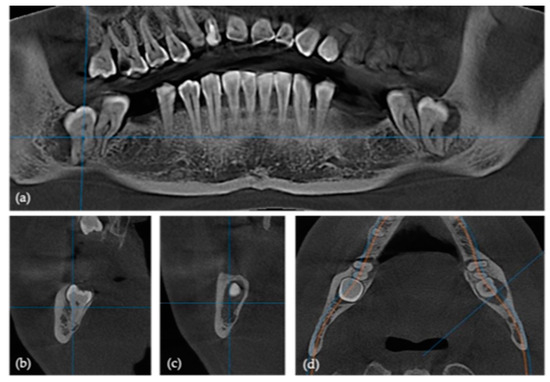

2.2. Pre-Surgical Cone Beam Computed Tomography (CBCT)

2.3. Design and Manufacturing of Customized Titanium Plates